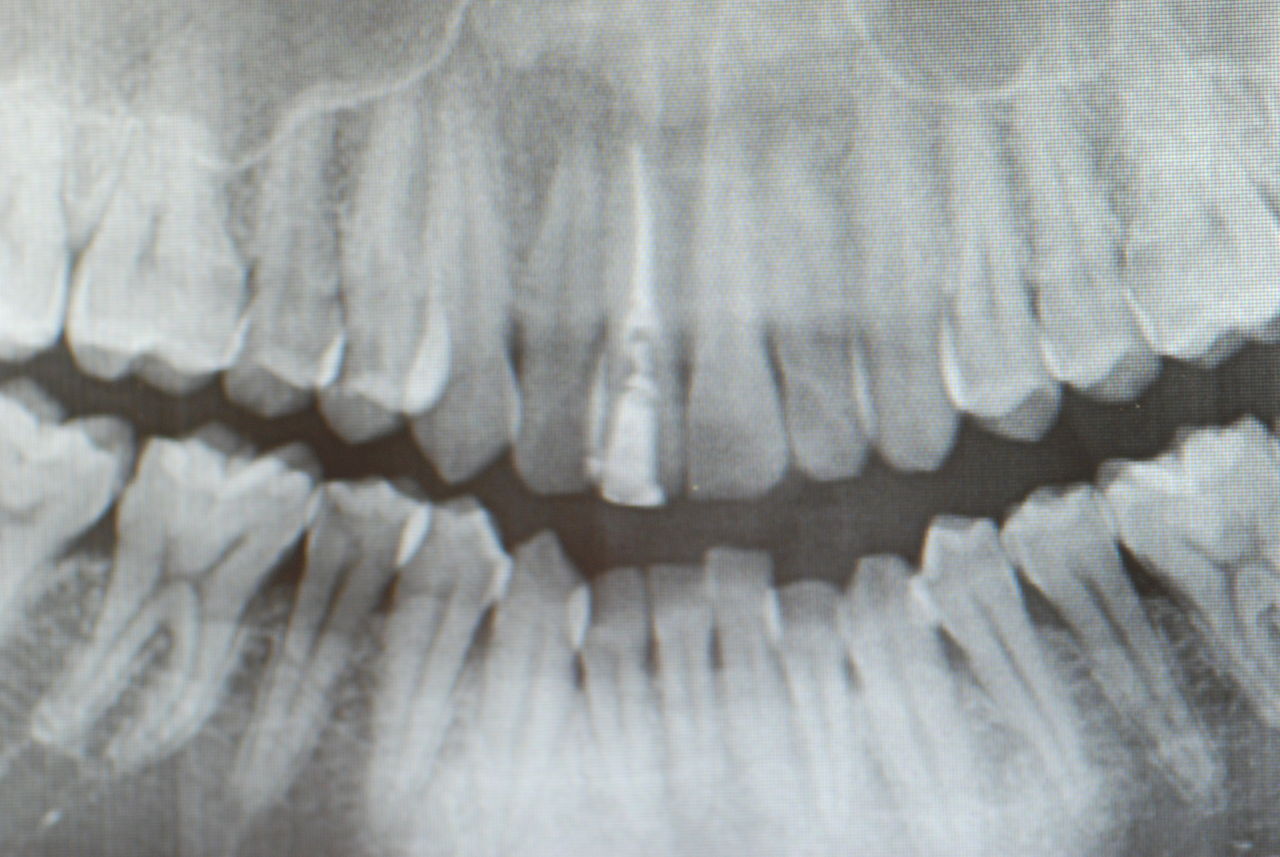

1、先ず一番目は、10才、右の前歯が反対咬合と言って上の歯と下の歯が逆の位置にあり、他の部分があまり咬合していない10才の子供の例でした。噛むと痛みが突然出てしばらく続いていたという症例。

診断を咬合性(歯と歯の噛みあわせ)の急性歯髄炎(神経の炎症)と判断したが、では治療はどうすればいいのかという相談。

レントゲンと話の内容から、食いしばりや歯ぎしりによるものではなく、単純にぶつかる歯が少ないので、その時に前歯のところで何か硬い物などを噛んだために外傷性の痛みが来たのではないかという判断でした。炎症でもないので、奥歯にマウスピースなどを入れて前歯を当たらなくした後に、症状が緩解したら、反対咬合という上下の前歯の関係を簡単な小矯正で変更した方がいいという診断と治療方針の提案で解決しました。

2、67才、女性、主訴は噛みあわせがおかしい。

矯正している。左の上下の6才大臼歯を保険の金属冠から都内の某所でジルコニアという硬いセラミック?冠に変えてからおかしくなっていったそうです。担当の歯科医師は削ったりしてどちらの歯も当たっていないぐらい削っているに違和感が取れないという主訴です。兵庫県の先生からの相談でした。

ここでも議論がわかずに、私も多分そうではないかと考えていたのですが、歯科心身症の方のようです。心身症というには、普通の方ですが、歯の部分の違和感や噛みあわせ云々と言われる方の殆どは、歯の治療に問題がなければ、歯科での治療に伴う異常な感覚がぬけなくなるという方がいるのです。